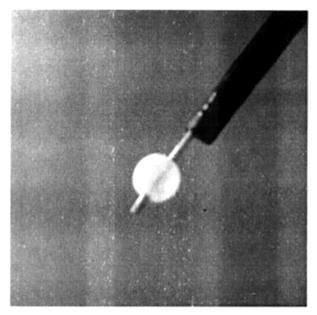

фиг. 2

«раздутый баллончик» на «дистальном конце литоэкстрактора».